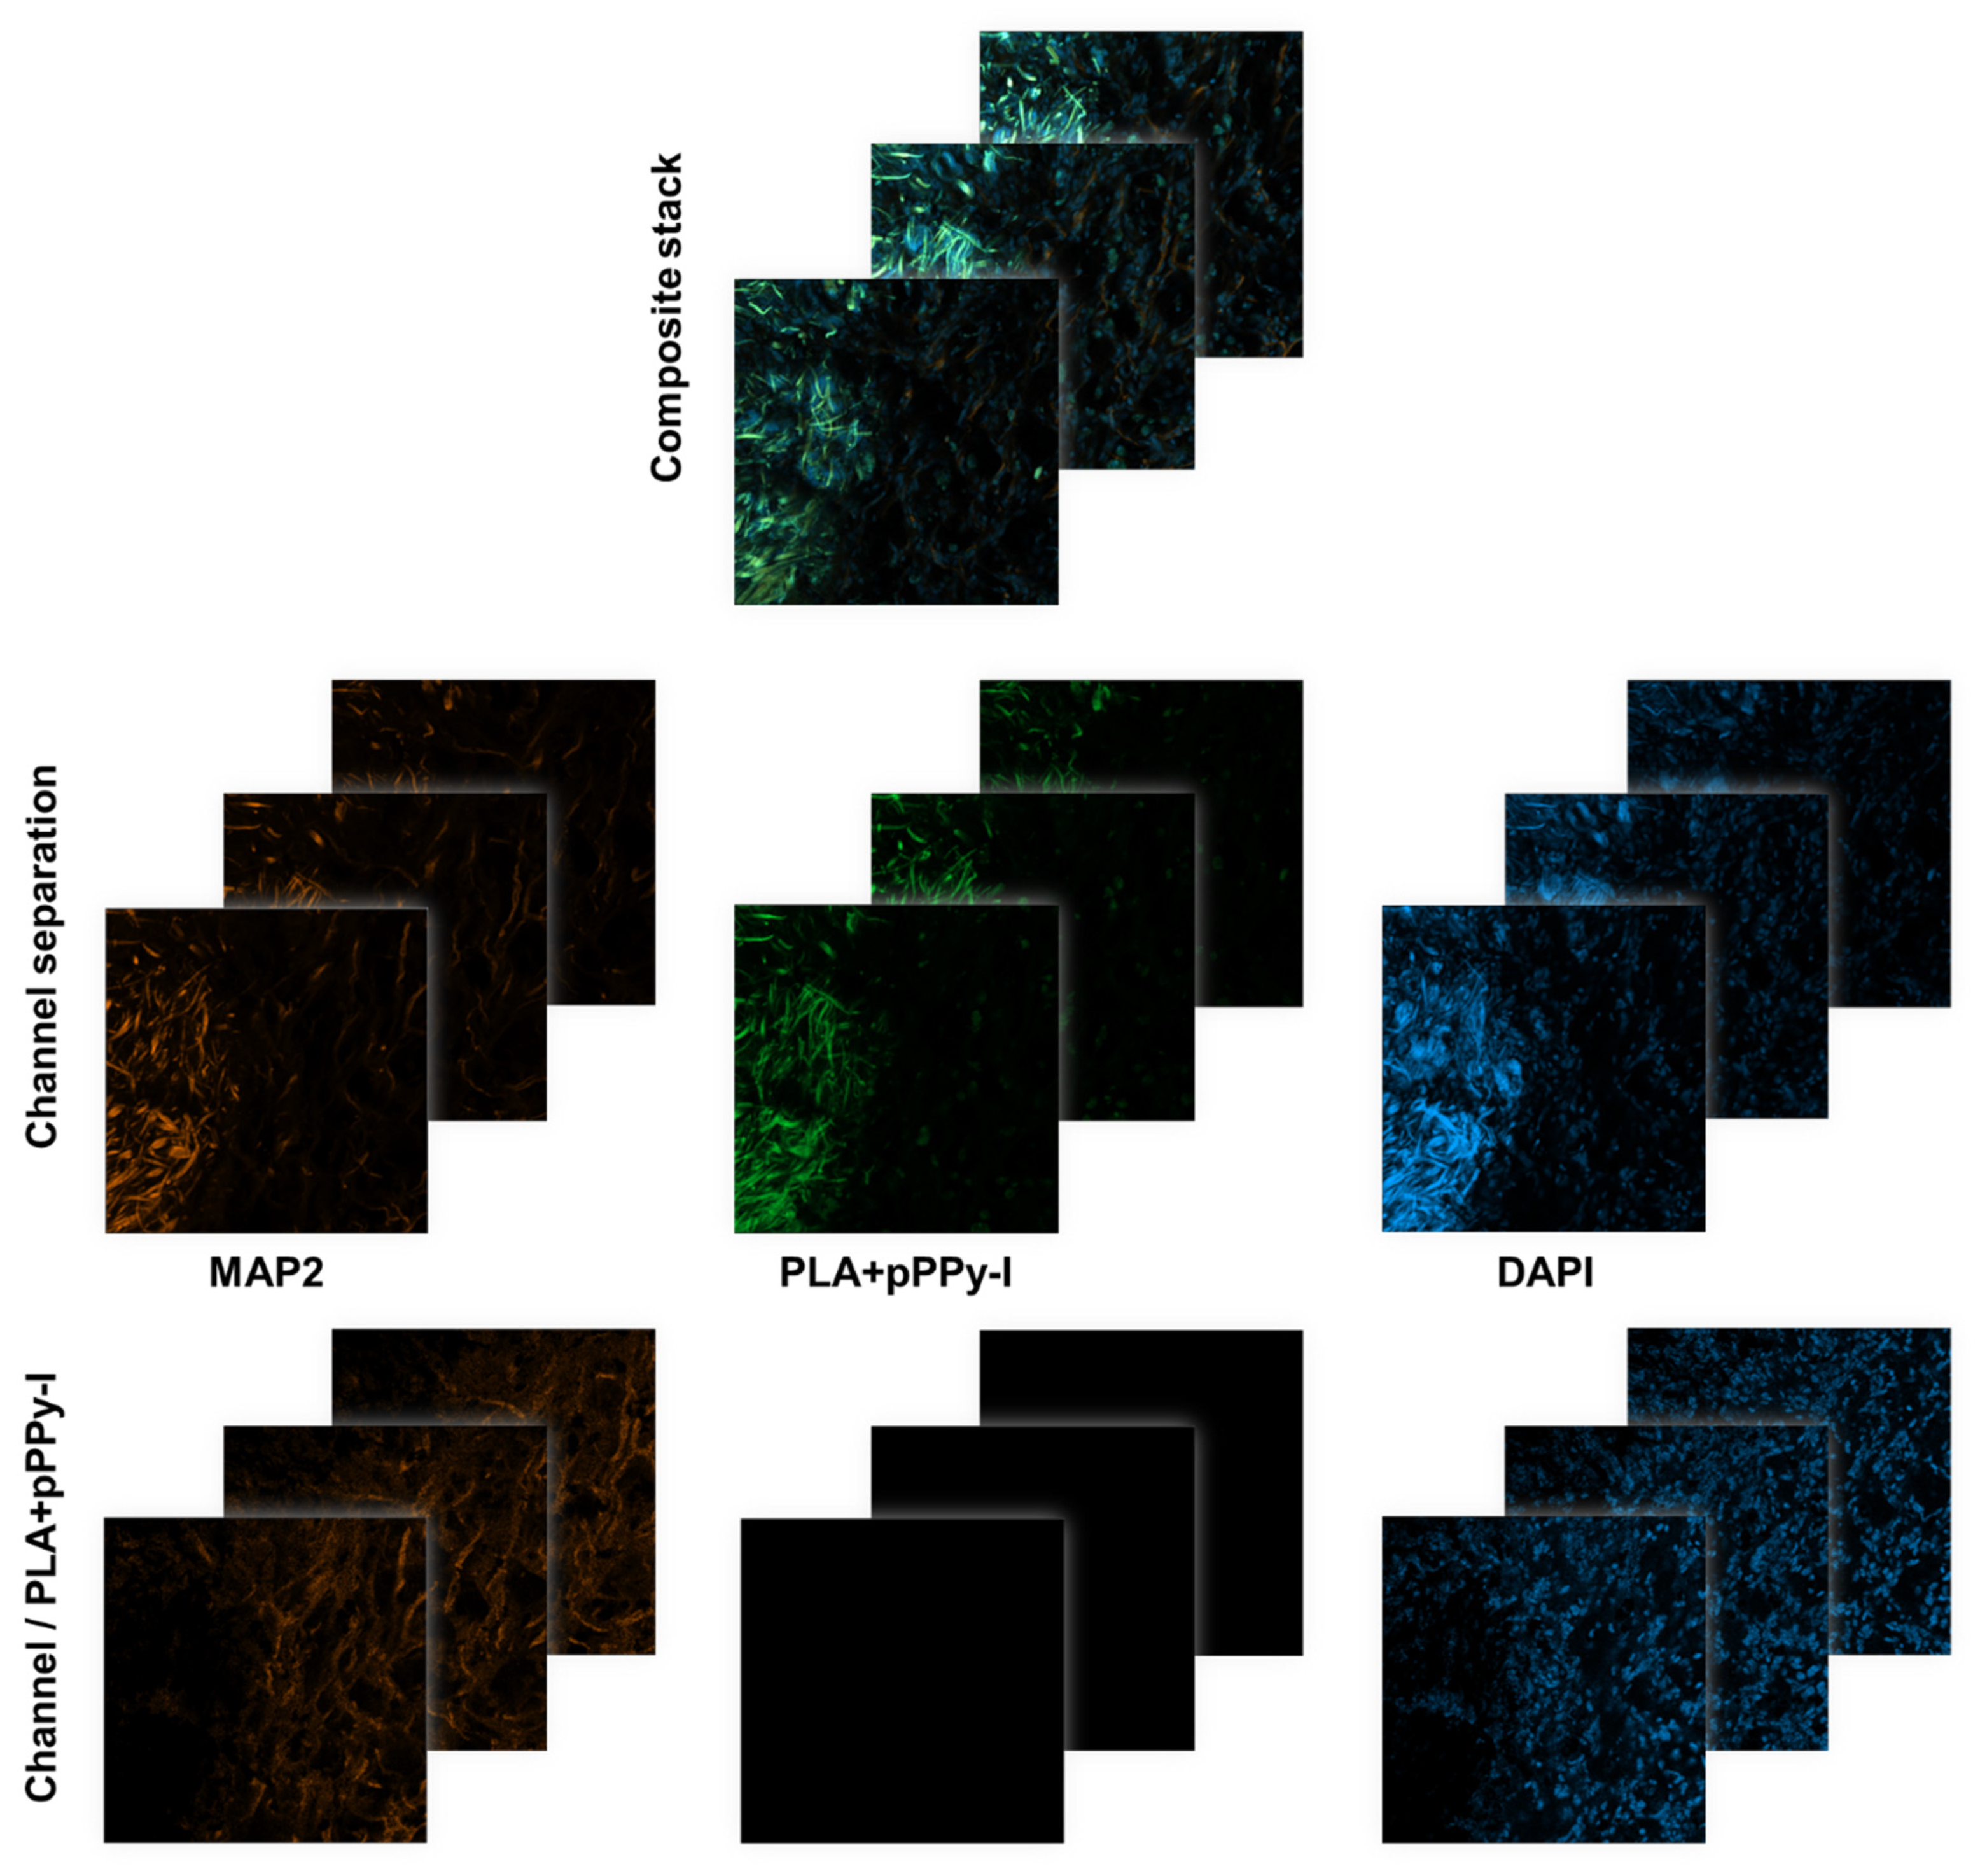

3.8. Evidence of Neuronal Marker MAP2 over the Fibers Demonstrated Fibrillar Scaffolds Are Potential Substrates for Nerve Repair